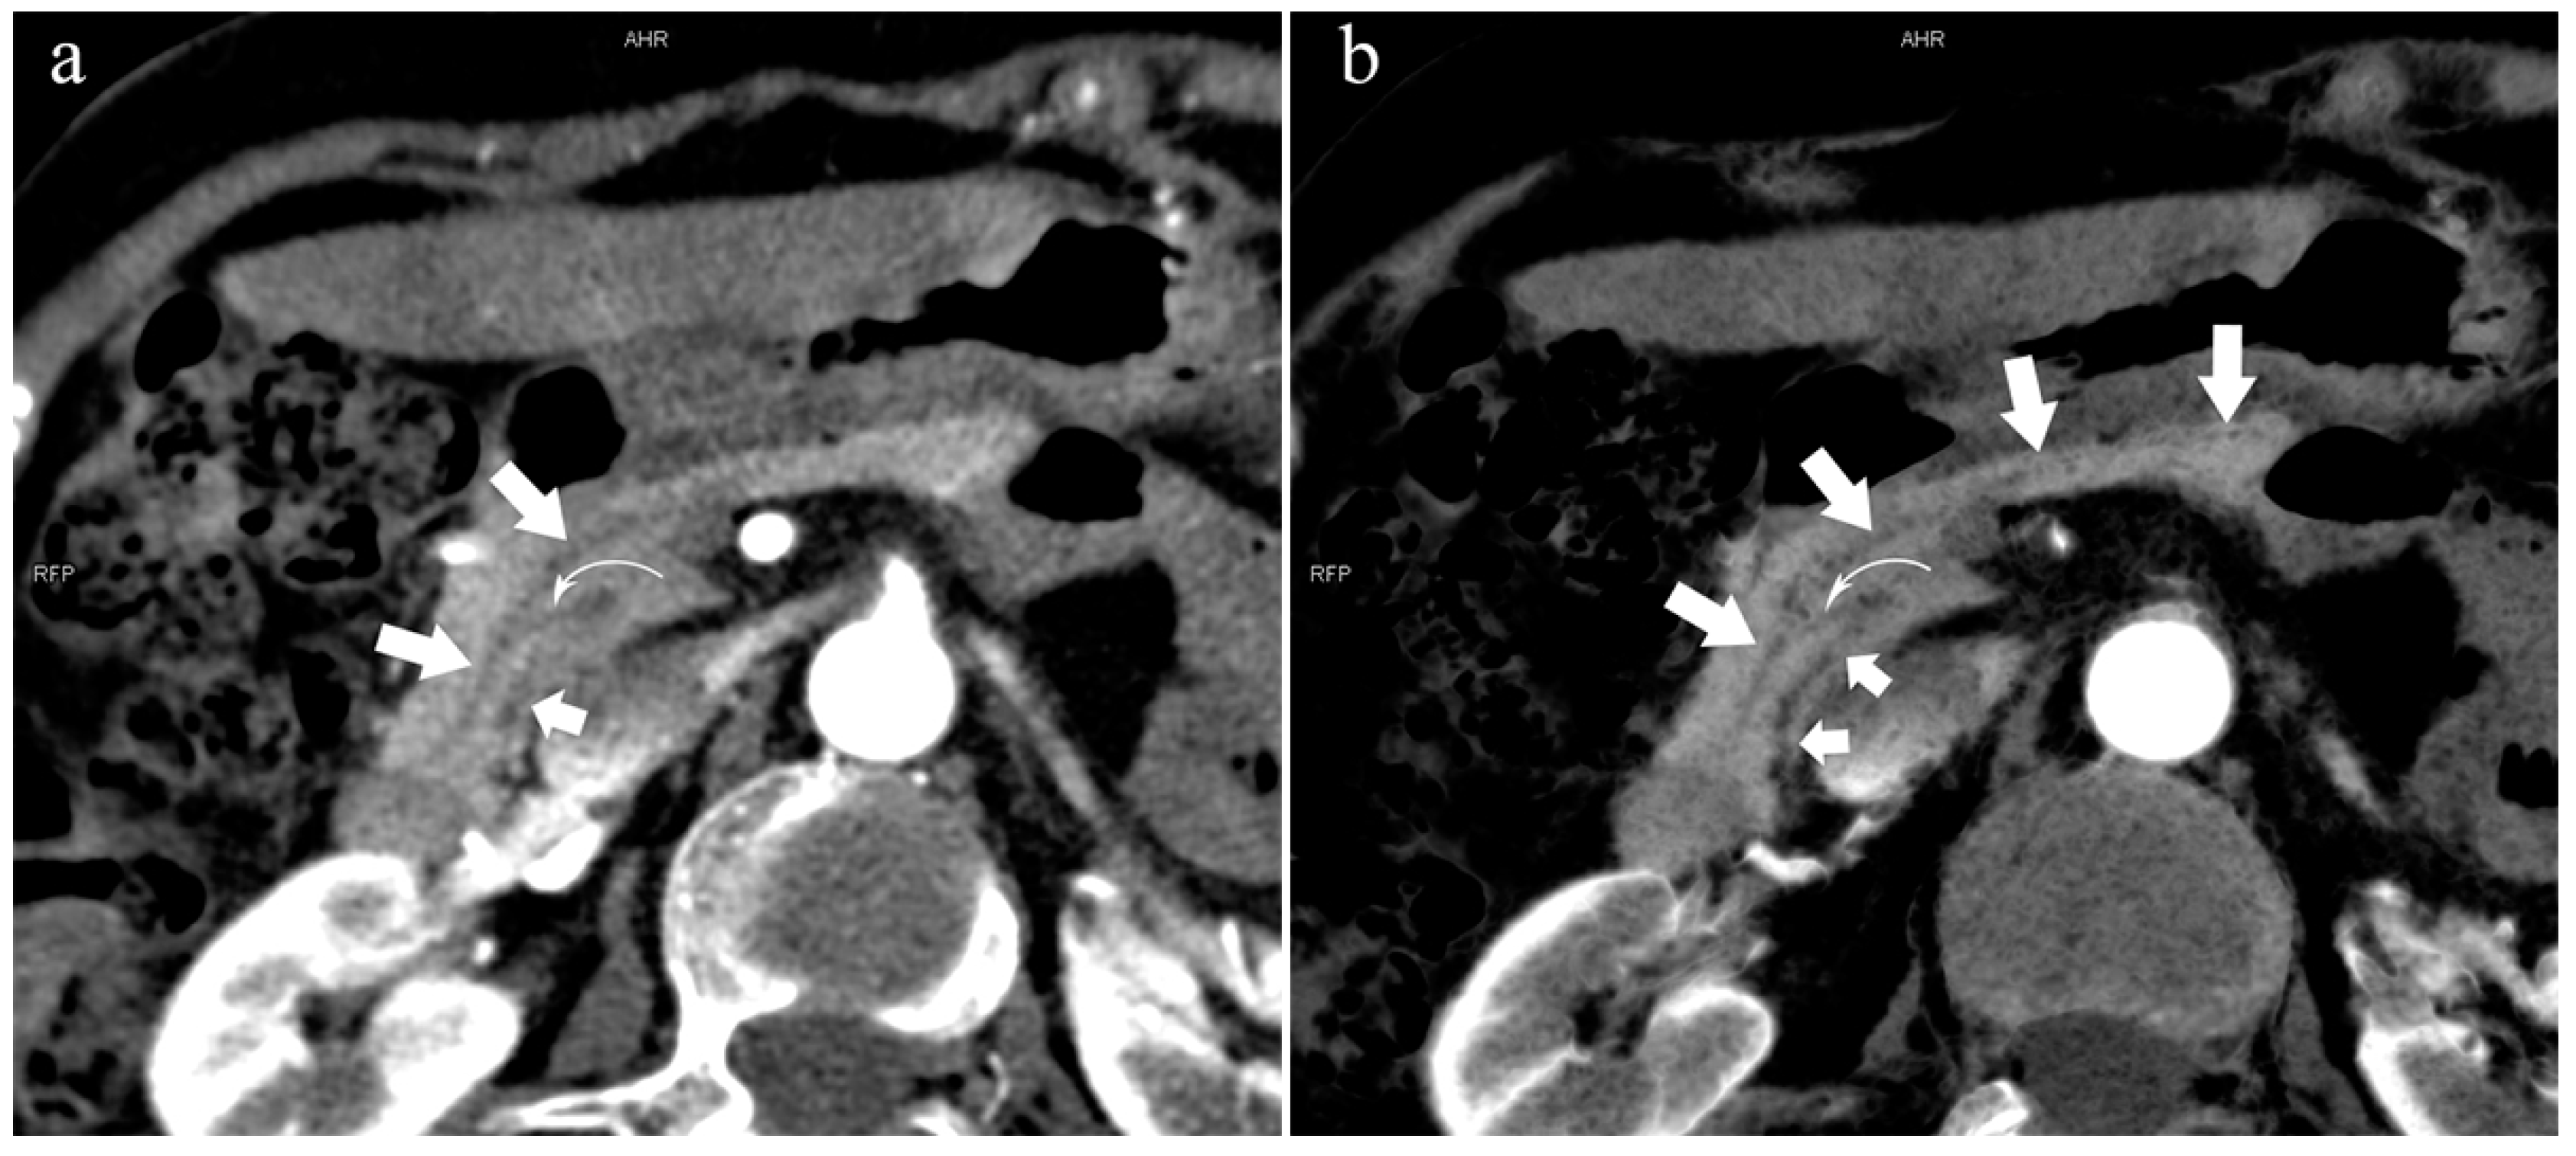

Figure 8.

Type 4c. A 73-year-old female patient with multiple stones of the intrahepatic bile duct. (a): MIP [45 keV MEI (+)] shows that MPD (long arrow) flows into MiP, and APD (short arrow) flows into MP with a small communication branch (bent arrows) between them. (b): MinIP [45 keV MEI (+)] improves visualization of small pancreatic ducts and their branches. MPD refers to anatomically large and functionally dominant ducts.